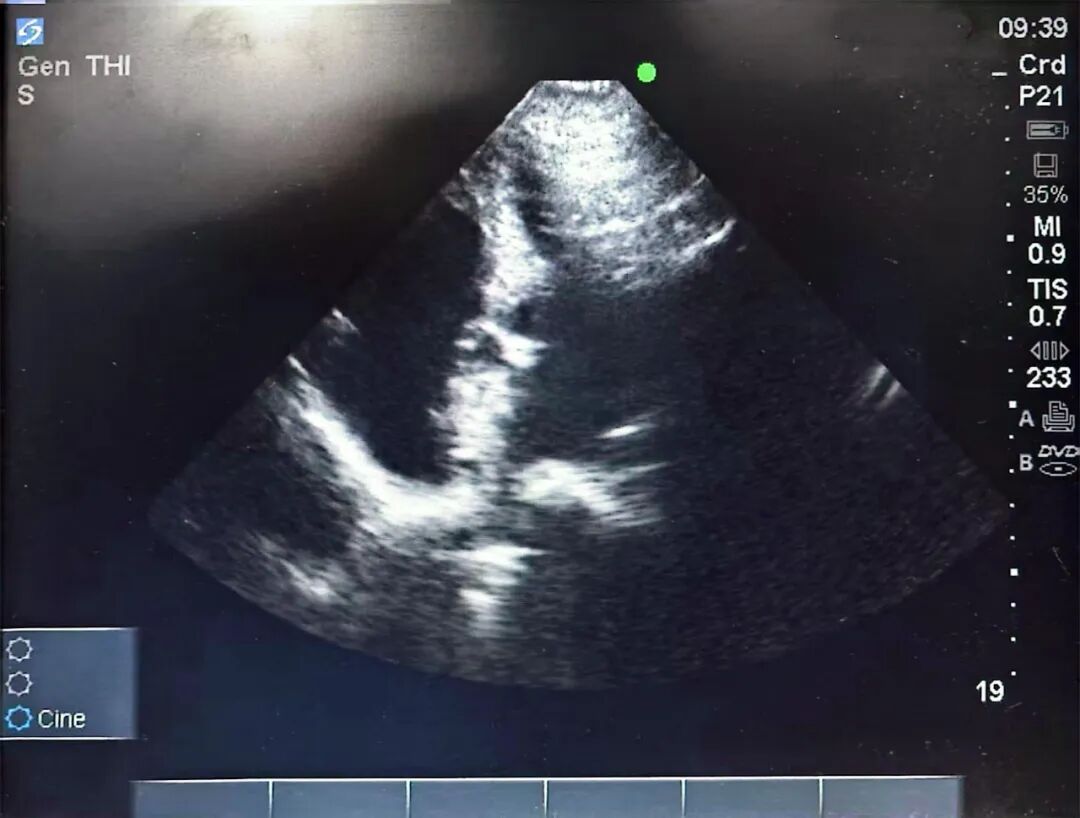

60岁的宋女士(化名),被反复发作的偏头痛折磨了很多年,还出现过隐源性脑卒中,严重影响工作与生活。来到长沙市第四医院心血管内科一病区就诊时,接诊医生为其安排了经右心声学造影(发泡实验)、经食道超声心动图检查,最终诊断为“卵圆孔未闭(PFO)”,且存在大量右向左分流,揪出了导致其顽固性头痛的“罪魁祸首”。

手术在局部麻醉下进行,艾旗凭借丰富的临床经验和精湛的介入技术,通过大腿根部的股静脉穿刺,送入一根细小的导管,在X线引导下,精准地将一枚形似“小伞”的封堵器输送至心脏卵圆孔处,一次性成功释放封堵器,关闭了异常通道。整个手术仅耗时30分钟。